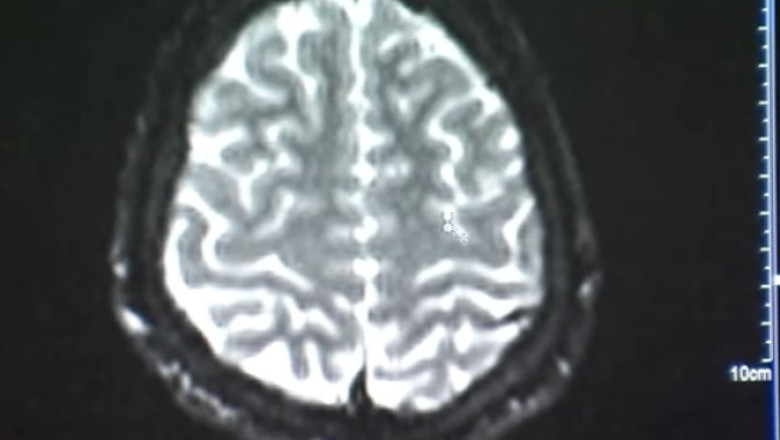

„Dacă apar leziuni demielinizante, deci sunt anumite modificări imagistice care coroborate cu datele din evaluarea noastră ne-ar duce cu gândul la un debut al unei boli de memorie şi în felul ăsta am putea actiona foarte bine pe segmentul de prevenţie”, a mai spus Luiza Spiru.

„Este vorba de aceste şenţulete care apar din exterior spre interiorul materiei cenuşii. Acestea ne arată nouă gradul de atrofie corticală”, a precizat Mihaela Camelia Minea.

De asemenea, sunt indicate analize speciale pentru a afla nivelul de serotonină, melatonină şi dopamină al fiecărei persoane, substanţe responsabile şi pentru îmbătrânirea prematură a creierului. În final, medicii recomandă efectuarea unui RMN, care va arăta în ce măsură creierul a fost afectat.